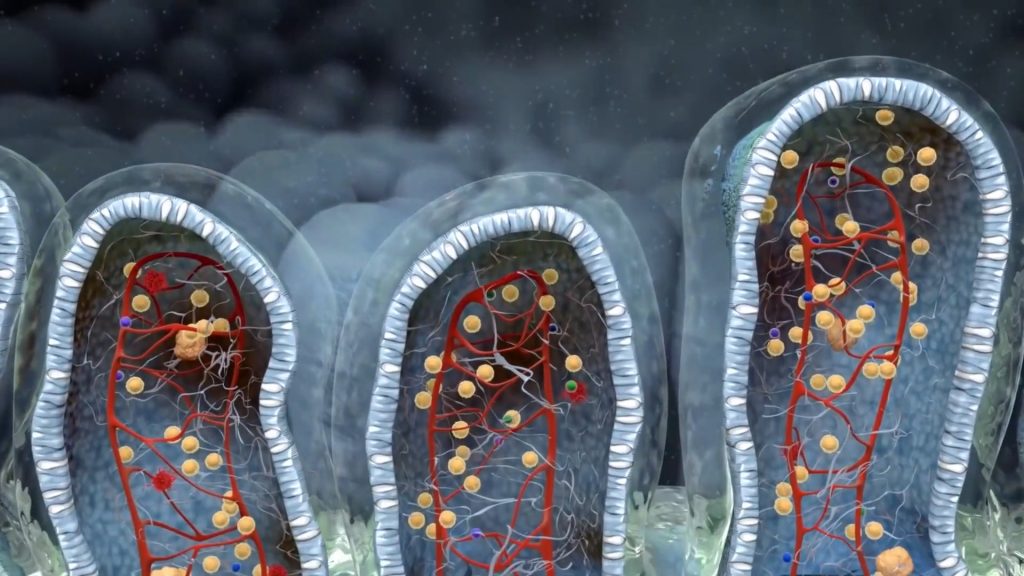

The main house cleaning mechanism of the small intestine is called MMC and is tightly regulated by the central nervous system itself, and mediated by the largest nerve of the human body, the vagus nerve. While describing this process here is of no use (it is fully detailed in MMC-SIBO chapter of the book), I need to pinpoint that there are several factors that may interfere with, delay or even inhibit completely MMC leading to bacterial overgrowth of the small intestine and as a result both upper and lower GI symptoms. Katherine fulfilled many prerequisites for MMC inhibition and thus the diagnostic panel was based on this hypothesis.

Migration motor complex

The cleaning machinery of the small intestine is regulated by the central nervous system itself. When in fasted state, muscular pulses directed by the brain forward all the debris produced by previous digestions from the small to the large intestine for elimination

Katherine’s results revealed a very intense SIBO produced gas signal along with a deeply disordered microflora. Besides commensal microbes whose levels were diminished, two Citrobacter species were detected in pathogenic amounts. Two many protein fragments were recovered on stool whereas several vitamin and nutrient deficiencies could be attributed to malabsorption. Finally, zonulin was recovered in very high levels indicating augmented intestinal permeability. Hashimoto’s and leaky gut are part of a vicious cycle. Thyroiditis delays MMC, leading to SIBO which in turn increases intestinal permeability and permits food antigens to get into circulation.

- Hashimoto's thyroiditis may directly interfere with the Migrating Motor Complex which is crucial for small intestinal cleaning after meals